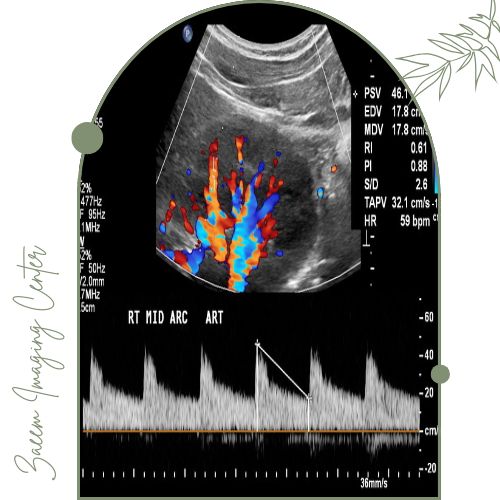

سونوگرافی کالر داپلر کلیه یک روش پیشرفته تصویربرداری غیرتهاجمی است که برای بررسی دقیق‌تر سلامت کلیه‌ها و عروق خونی آن‌ها به کار می‌رود. آنچه این روش را از سونوگرافی معمولی متمایز می‌کند استفاده از فناوری «داپلر رنگی» است. در این تکنیک دستگاه قادر است حرکت گلبول‌های خون در رگ‌های کلیه را ردیابی کرده و سرعت و جهت جریان خون را در قالب رنگ‌های مختلف (معمولاً قرمز و آبی) نمایش دهد. این کدگذاری رنگی به پزشک اجازه می‌دهد تا مسیر و شدت جریان خون را به راحتی مشاهده کند و هرگونه اختلال مانند تنگی عروق یا انسداد را به سرعت تشخیص دهد.

تفسیر نتایج بر اساس معیارهای مشخصی انجام می‌شود که عمدتاً به سرعت جریان خون، الگوی عبور خون از شریان‌ها و شاخص مقاومت عروقی وابسته است.

در حالت طبیعی جریان خون در شریان‌های کلیوی یکنواخت و سرعت آن متناسب با وضعیت کلیه است.

اگر تنگی یا انسداد وجود داشته باشد، معمولاً سرعت خون در نقطه خاصی افزایش یافته و شاخص مقاومت تغییر می‌کند.

همچنین رادیولوژیست با مشاهده رنگ‌های خاص در تصویر می‌تواند اختلالات جریان، وجود لخته یا آسیب عروقی را تشخیص دهد.